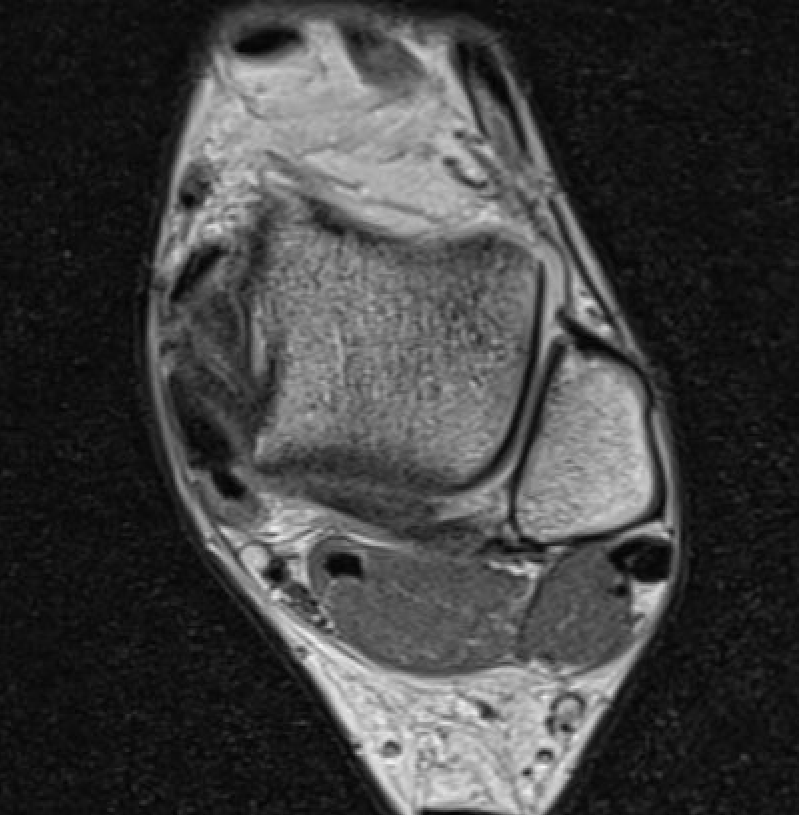

MRI

ATFL tear

CFL tear